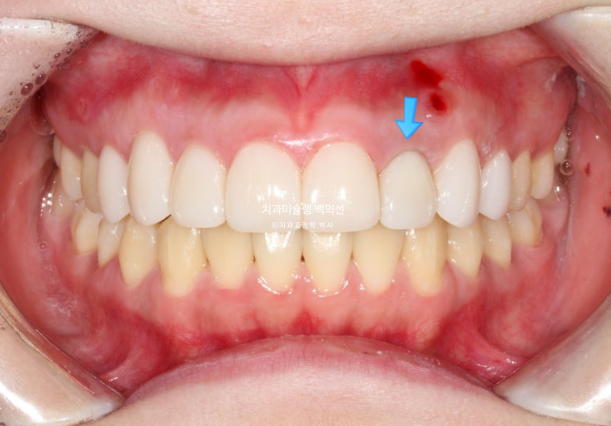

환자분이 교정 마무리 후 타병원에서 무삭제라미네이트를 하고 오셨습니다.

25.08

신경 치료 후 까맣게 변색이 된 앞니는 실활치미백으로 치아 내부부터 변색을 제거한 뒤에 무삭제 라미네이트를 하는 것이 좋습니다.

그렇지 않으면 까만 부분이 잇몸과 라미네이트 사이로 비쳐나오게 됩니다.

라미네이트 두께나 투명도도 그렇고 좀 아쉽습니다.

이제 전후 비교해보겠습니다.

총 치료기간은 1년 7개월, 재제작은 1회 했습니다.

23.12~25.08

맞아진 중심선과 배열의 개선이 보입니다.